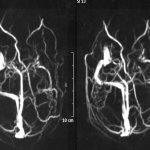

• MRI helps to identify the morphological substrate. To diagnose the slightest structural changes, a minimum thickness of sections is required. With symptomatic FE, it is possible to establish the underlying disease and note dysplastic transformations. If there are no abnormalities during magnetic resonance imaging, cryptogenic or idiopathic focal epilepsy is diagnosed.

MRI: slight expansion of the subarachnoid spaces in the frontal areas. No focal structural changes in the brain substance were detected.